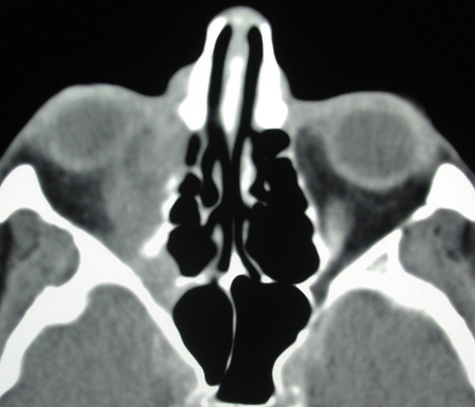

Computed tomographic findings in patients with both forms of the disease demonstrate areas that are almost metallic in density. These foci of irregularly calcified bone on CT may be pathognomonic (Fig. 22). On MRI, these areas appeared bright on T1-weighted imaging and have decreased signal on T2-weighted images, which may be related to the presence of ferromagnetic materials such as iron and manganese within the fungal concretions.115

Fig. 22. Aspergillosis. Computed tomography shows areas of extreme density of the ethmoidal bones.